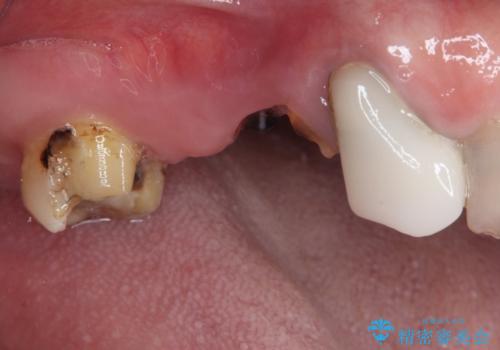

- 欠損や破折により失われた奥歯に、インプラント治療を希望して来院された患者様です。

欠損部はすぐにインプラント埋入が可能で、手前の歯根が残存している部位も、できれば抜歯をして奥と一緒に埋入をしたいところでしたが、破折による炎症が大きいため、2回に分けてインプラント埋入を行うこととしました。